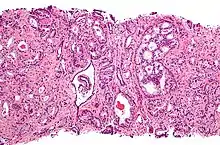

Histopathologic diagnosis

A histopathologic diagnosis mainly includes assessment of whether a cancer exists, as well as any subdiagnosis, if possible. Histopathologic subdiagnosis has implications for the possibility and methodology of Gleason scoring.[85] The most common histopathological subdiagnosis is acinar adenocarcinoma, constituting 93% of diagnoses.[86] The most common form of acinar adenocarcinoma, in turn, is "adenocarcinoma, not otherwise specified", also termed conventional, or usual acinar adenocarcinoma.[87]

After a biopsy, a pathologist examines the samples under a microscope. If cancer is present, the pathologist reports the grade of the tumor. The grade tells how much the tumor tissue differs from normal prostate tissue and suggests how fast the tumor is likely to grow. The pathologist assigns a Gleason number from 1 to 5 for the most common pattern observed under the microscope, then does the same for the second-most common pattern. The sum of these two numbers is the Gleason score. The Whitmore-Jewett stage is another method.